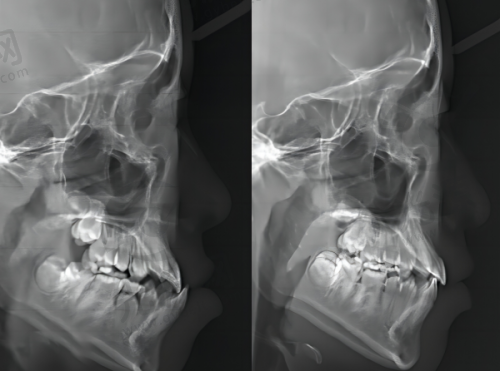

其次,医院拥有精良的数字化设备。例如在拔牙时采用数字化设备定位,能实现微创拔牙,减少患者的创伤;在种植牙方面,数字化种植技术成熟,提供3D导板定位。